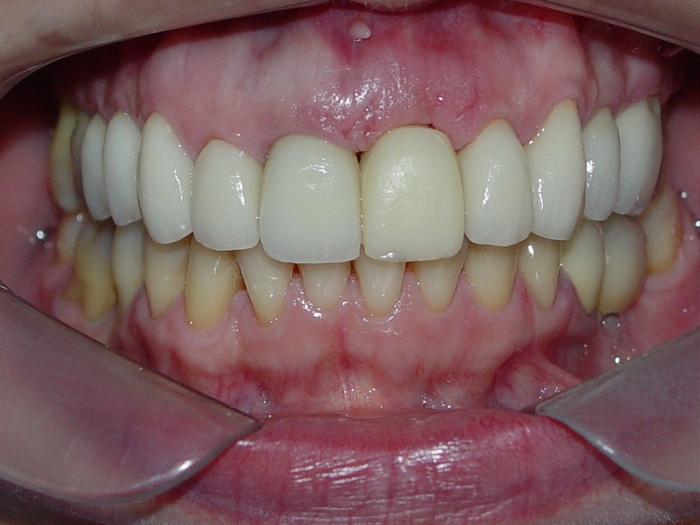

Sorriso inicial